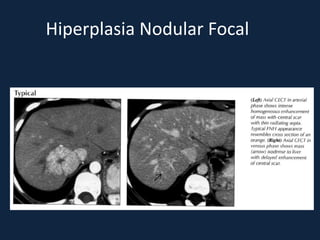

Hiperplasia Nodular Focal

► 2º tumor hepático benigno mais comum

► Resposta hepática hiperplásica (Proliferação de hepatócitos,

células de Kupffer, ductos biliares primitivos e vasos

sanguíneos) a uma anormalidade vascular local.

► ♀ de meia-idade

► NÃO relacionada a ACO, embora este tenha um efeito trófico

► Geralmente solitária (80%), menores que 5 cm, de localização

subcapsular e no lobo direito (2:1).

► Assintomática.

► s/c: lesão bem delimitada, homogênea isodensa ou

discretamente hipodensa.

► c/c: realce intenso, precoce e fugaz.

– Fase arterial: acentuado realce homogêneo, exceto pela cicatriz

central.

– Fase portal: hipo ou isodensa ao parênquima hepático. Início do

realce da cicatriz.

– Fase tardia: isodensa ao parênquima hepático, com realce da

cicatriz.